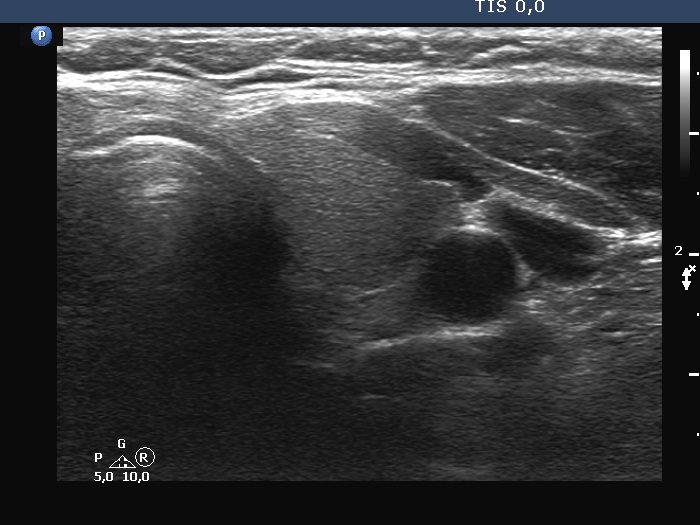

Ultrasonography. The thyroid was echonormal. There was a dominantly solid nodule in the right lobe. The lesion showed back wall cystic figures caused by posterior enhancement and nonparallel orientation. The depth of the nodule was 12 mm while the width was 10 mm.